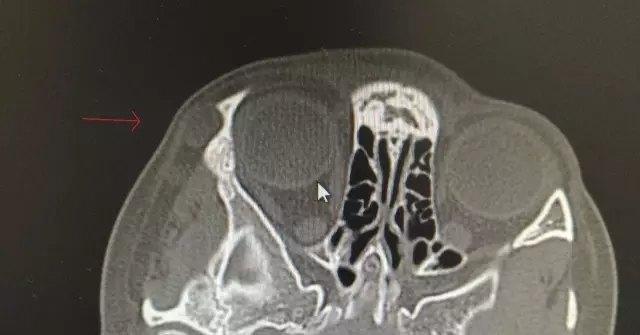

虽然表皮样囊肿相对表浅,但有的可以长得很深很大,甚至深达眼眶内,造成取出困难,甚至会损伤周边重要的组织